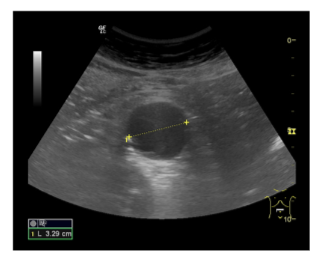

Informe: Hígado de tamaño y ecogenicidad normal. Vesícula distendida con 2 litiasis de 2 x 3 mm en su interior. Páncreas y bazo de ecoestructura normal. Ambos riñones de tamaño, ecogenicidad en rango, diferenciación corticosinusal. Vena porta, cava inferior y aorta en el área del lóbulo hepático izquierdo de calibre normal. Aneurisma de aorta abdominal descendente hasta su bifurcación de ambas iliacas de 3.29 cm en su eje trasversal con engrosamiento de pared posterior.